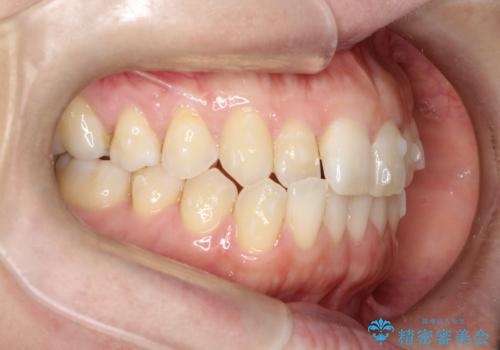

上の歯と下の歯が反対にかんでいる インビザラインによる目立たない矯正

- 右上の前から2番目と3番目の歯が内側に引っ込んでしまっているのを主訴に来院されました。

右上の2番目と3番目のはが前後反対にかんでしまっている状態でした。

内側に引っ込んでいる歯も、インビザラインにてしっかり外側に動かすことができます。